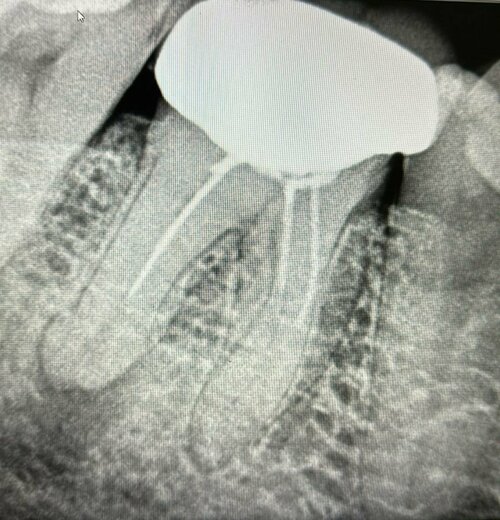

Dr. Gautami Phadke, Consultant Dental Surgeon and Root Canal Specialist, successfully treated a case of decay in the anterior (front) teeth. The patie...

At Phadke Dental Clinic, Dr. Gautami Phadke recently treated a patient suffering from severe pain due to a failed root canal procedure performed elsew...